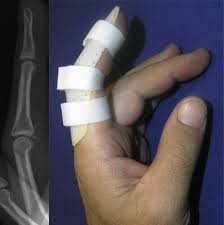

Как и при любых других переломах, все мероприятия по лечению сломанной фаланги направлены на то, чтобы помочь ей правильно и как можно быстрее срастись. Для этого палец необходимо надёжно зафиксировать в выравненном положении и обеспечить ему полную неподвижность. Осуществить это возможно по средствам наложения гипса, фиксирующего ортеза, либо специальной полимерной повязки. Как правило, в первые несколько дней после перелома, пациенту может быть назначено лёгкое болеутоляющее. Так же возможно назначение всевозможных кальцийсодержащих препаратов, которые способны посодействовать быстрейшей регенерации костной ткани.

В случае, когда перелом фаланги со смещением привёл к травмированию ближайших органов (сухожилий, суставов) и физиологическому изменению строения пальца, единственное правильное решение — это проведение оперативного вмешательства. Осуществляется оно под местным наркозом. Врач во время операции возвращает обломки кости в правильное положение и проводит санацию близ лежащих органов и тканей. По окончании данной медицинской манипуляции повреждённый орган фиксируется с помощью ортеза. Другие варианты фиксации в данном случае не подойдут. Дело в том, что в послеоперационный период место разреза будет необходимо обрабатывать и наблюдать, а именно с помощью ортеза возможно и надёжно зафиксировать поломанный орган и иметь доступ к некоторым его частям. На протяжении нескольких дней после оперативного вмешательства пациенту, на ряду с обезболивающими препаратами, нередко назначают ещё и курс антибиотиков.